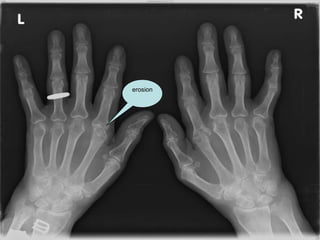

Investigation RF  458 FBC  (N) ESR  39 CRP  50 U&E  (N),  LFT  (N) X-ray hands, Feet & CXR

erosion

Treatment LO-RA:  MTX (10mg O/W & increase dose if no SE) If erosion increase MTX dose & added HCQ PMR: 15 mg prednisone dramatic response  MTX (as steroid sparing) 87.5% of MTX-treated patients and 53.3% of patients treated with prednisone alone were no longer on steroids at 76 weeks. Significantly fewer patients on MTX had at least one flare up by the end of follow-up.  Infliximab  in the treatment of polymyalgia rheumatica: a double-blind, randomized, placebo-controlled study. Salvarani C, Macchioni PL, Manzini C, et al.  Ann Intern Med (2007)   no differences  were observed among groups: the proportion of patients who were free of relapses/recurrences at 22 and 52 weeks  was similar   reducing dose of steroid  should be based on sign & symptoms  rather than CRP & ESR value,  which dose not predicate relapse Therapy usually last two years,  relapse usually in  the 1st or 2nd month